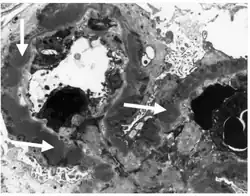

-

Subepithelial dense deposits and basement membrane reaction arrows -

Immune complexes (black) are deposited in a thickened basement membrane creating a "spike and dome" appearance on electron microscopy.

Diagnosis is by a kidney biopsy.[1] The defining point of MGN is the presence of subepithelial immunoglobulin-containing deposits along the glomerular basement membrane (GBM).

- By light microscopy, the basement membrane is observed to be diffusely thickened. Using Jones' stain, the GBM appears to have a "spiked" or "holey" appearance.

- On electron microscopy, subepithelial deposits that nestle against the glomerular basement membrane seems to be the cause of the thickening. Also, the podocytes lose their foot processes. As the disease progresses, the deposits will eventually be cleared, leaving cavities in the basement membrane. These cavities will later be filled with basement membrane-like material, and if the disease continues even further, the glomeruli will become sclerosed and finally hyalinized.